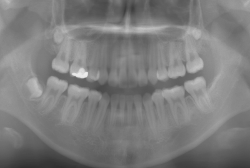

「左奥歯でものが噛めない」という主訴で来院したケースです。診断の結果、基本的には「叢生」という隙間が足りないと言うことが原因の凸凹症例でしたが、左下の乳歯が高校生になってもまだ残存している状態で、そのせいで噛み合わせが極端に悪くなっていました。

検査の結果、乳歯の下には後継ぎの永久歯が先天的に欠如していました。配列の凸凹が厳しく非抜歯で矯正することは難しく、仮に無理をして非抜歯治療をしても後々「後戻り」が懸念されることから、このような症例の場合は通常、上下顎左右第一小臼歯を抜歯させていただくのですが、左下は乳歯を抜歯して、第一小臼歯は残すことにしました。これで結果として、小臼歯部を上下左右で一つずつ減らしたのと同じ状況になります。治療後は歯並びが綺麗になっただけでなく、噛み合わせ的にも正しい状態が確立しています。

このように、先天的に永久歯が足りないという症例は最近増えています。親知らずはなくても特に問題になりませんが、その他の歯が足りないと言うのは審美的にも機能的にも重大な障害となります。しかし、矯正治療を正しく行えば、結果として歯がすべてあった場合と全く同じ仕上げにすることも可能です。